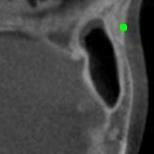

Detecting 3D landmarks on cone-beam computed tomography (CBCT) is crucial to assessing and quantifying the anatomical abnormalities in 3D cephalometric analysis. However, the current methods are time-consuming and suffer from large biases in landmark localization, leading to unreliable diagnosis results. In this work, we propose a novel Structure-Aware Long Short-Term Memory framework (SA-LSTM) for efficient and accurate 3D landmark detection. To reduce the computational burden, SA-LSTM is designed in two stages. It first locates the coarse landmarks via heatmap regression on a down-sampled CBCT volume and then progressively refines landmarks by attentive offset regression using multi-resolution cropped patches. To boost accuracy, SA-LSTM captures global-local dependence among the cropping patches via self-attention. Specifically, a novel graph attention module implicitly encodes the landmark's global structure to rationalize the predicted position. Moreover, a novel attention-gated module recursively filters irrelevant local features and maintains high-confident local predictions for aggregating the final result. Experiments conducted on an in-house dataset and a public dataset show that our method outperforms state-of-the-art methods, achieving 1.64 mm and 2.37 mm average errors, respectively. Furthermore, our method is very efficient, taking only 0.5 seconds for inferring the whole CBCT volume of resolution 768$\times$768$\times$576.